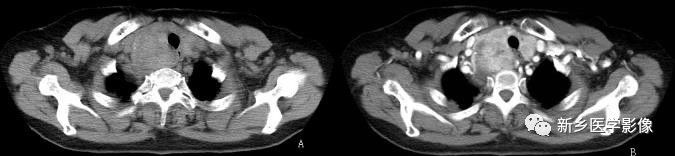

胸内结节性甲状腺肿CT图像

a. CTCT平扫示上纵隔气管两侧甲状腺软组织密度肿块,密度欠均匀,气管受压移位、变形 b. 增强后明显不均匀强化